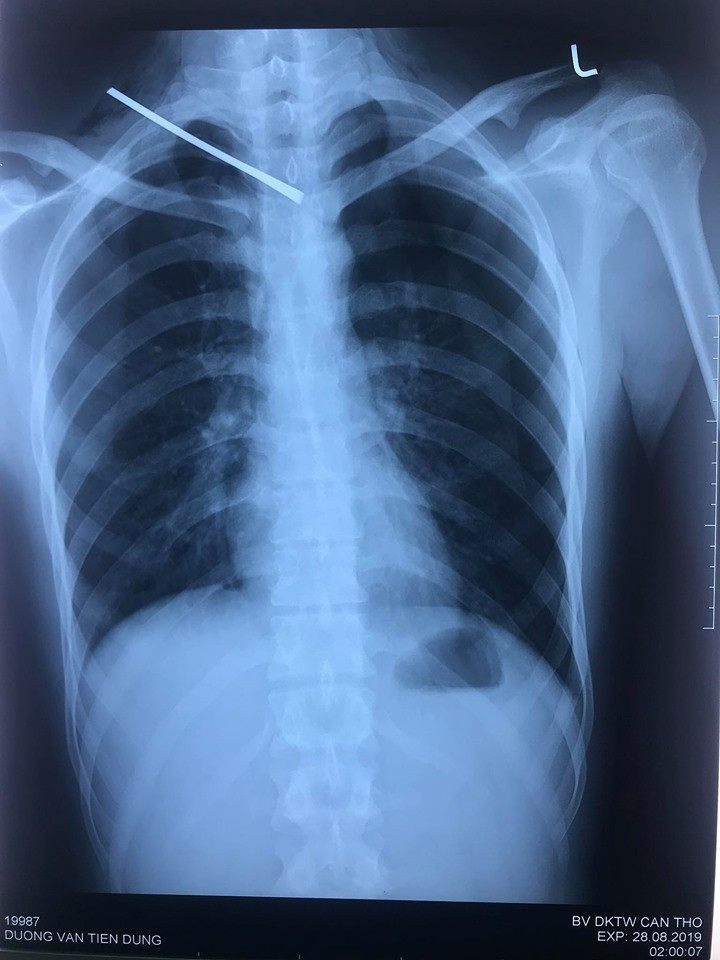

Bệnh nhân được thực hiện các xét nghiệm, kết quả X-quang tim phổi thẳng và CT64 lát cột sống cổ không cản quang cho thấy: Dị vật kim loại đường kính 0.5cm dài 10cm xuyên từ vùng cổ phải đến khe gian đốt sống D3-D4 chèn vào mặt trước ống tủy, tụ khí dưới da vùng cổ ngực hai bên, tràn khí và ít dịch màng phổi phải, tràn khí màng phổi trái.

| Hình ảnh phim chụp. |